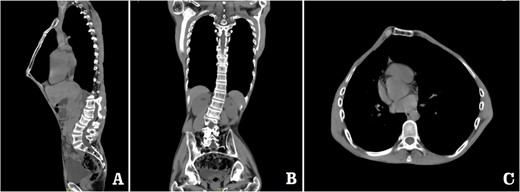

The patient was a 29-year-old male. He was found to have protrusive deformity on the anterior chest wall since childhood. The deformity was not serious in early years, but worsened after adolescence, with the lower part of the sternum protruding at an acute angle. At the age of 25, he developed right spontaneous pneumothorax and received surgical treatment at local hospital, but his thoracic deformity was not treated. As the deformity continued to worsen, which seriously affected the appearance of the chest wall, the patient was admitted to our hospital for surgery. Preoperative physical examination showed that the anterior chest wall was protrusive seriously, with a sharp tip protruding forward. The rib arches on both sides were slightly depressed (Fig. 1). Imaging examination showed that the anterior chest wall was protrusive, and the lower end of the sternum was at the forefront of the protrusion. His heart moved to the right, and the rib arches were slightly depressed (Figs 2–4). The operation was performed under general anesthesia. Two longitudinal incisions were made on both sides of the chest wall respectively. The incisions were located between the front axillary line and the median axillary line, with the length of ~5 cm. The chest wall muscles were dissected to expose the ribs in the incisions. Two tunnels were made on the highest plane of the protrusion, with interval of 3 cm. The tunnels were located in the deep layer of the chest wall muscles and bone structures. Two steel bars were inserted into the tunnels to flatten the front protrusion with their median parts, and then, both ends of the steel bars were fixed on the ribs at the lateral chest wall. The above operation was the main content of Wenlin procedure [1, 2, 5]. After this procedure was completed, the lower part of the chest wall showed obvious depression, especially in the middle of the rib arches. Then, Wung procedure was performed [6]. A third tunnel was made at the plane passing the midpoint of the rib arch, which passes through the bilateral thoracic cavity. The third steel bar was inserted into the tunnel. After the steel bar was rotated and fixed to the ribs, the depression was supported totally. The incisions were closed, and the operation was completed. The deformity of anterior chest wall disappeared completely after the operation (Fig. 5). The operation time was 75 min. The intraoperative bleeding volume was 40 ml. Postoperative X-ray examination showed that the bars position was normal (Fig. 6). He was discharged 7 days after operation. Follow up for 1 year showed satisfactory recovery. The steel bars were taken out 1 year after the operation, and the appearance of the thorax was normal and there was no recurrence (Fig. 7).

Computed tomography examination before operation. (A) Sagittal view; (B) coronal view; and (C) sectional view.